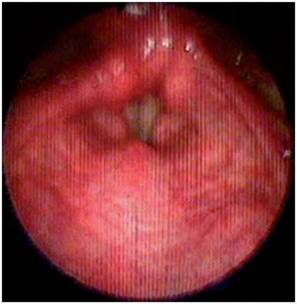

<p>El paciente paulatinamente presentó mejoría de la visión borrosa y principalmente de la disfagia y vértigo, hacia la semana siguiente ya podía alimentarse sin dificultad y mejoró la fuerza del hemicuerpo izquierdo completamente. Se dio egreso del hospital solo con leve disfonía, anhidrosis hemicara izquierda y marcha atáxica leve lográndose desplazar con bastón. En el seguimiento, luego de 1 y 3 meses posterior al inicio de los síntomas, el paciente retornó a su estado funcional previo y solo persistió con disfonía, la cual se explicó por la parálisis de la cuerda vocal izquierda que se confirmó por estudio de nasofibrolaringoscopia (<xref ref-type="fig" rid="f7">figuras 7</xref>,<xref ref-type="fig" rid="f8">8</xref>). El paciente dio su consentimiento para realizar la publicación de su caso.</p>

<p>El paciente se caracterizó por tener principalmente dis-fagia, disfonía, vértigo, ataxia y hemiparesia ipsilateral, las cuales rápidamente mejoraron, siendo llamativo la ausencia de nistagmo el cual se reporta en una incidencia importante. El estudio por resonancia magnética se logró realizar 1 semana posterior al inicio de los síntomas, lo cual generó la limitante de observar pseudo-normalización en la secuencia DWI (Diffusion Weighted Imaging) y por ende ausencia de una clara restricción de la difusión. En el T2 corte coronal se puede ver extensión hacia zonas caudales de la unión bul-bomedular, lo cual explicaría por qué presentó compromiso del tracto cortico-espinal siendo la primera causa, la lesión de las fibras ya decusadas provenientes del hemisferio contrala-teral ya sea por isquemia o por efecto de masa por el edema adyacente, este hallazgo se correlaciona con lo mayormente reportado en otras publicaciones. Un elemento importante en el paciente fue el inicio súbito de los síntomas posterior a realizar una rotación brusca del cuello con dolor cervical asociado, lo cual debe ubicar al clínico en un contexto cuya principal etiología a estudiar sea la disección cervical dada además la ausencia de factores de riesgo cardiovasculares y la edad cercana a los 50 años, sin embargo, en una angiografía convencional tomada 3 semanas después, no se evidenció esta etiología según lo informado por radiología. A pesar del compromiso motor, no todos los pacientes que cursan con síndrome de Opalski tienen una afectación marcada de la funcionalidad e independencia <xref ref-type="bibr" rid="B17"><sup>17</sup></xref> y la debilidad evidenciada es leve y transitoria permitiendo su recuperación hasta el 100 % previo, como se observó en este caso. Por otro lado, es importante evitar complicaciones tempranas como la broncoaspiración y neumonitis secundaria y, por ende, se hace imperativo plantear desde el ingreso de estos pacientes una vía alterna de alimentación a través de sonda naso u orogástrica o gastrostomía mientras se lleva a cabo el proceso de rehabilitación de la disfagia de forma paralela.</p>